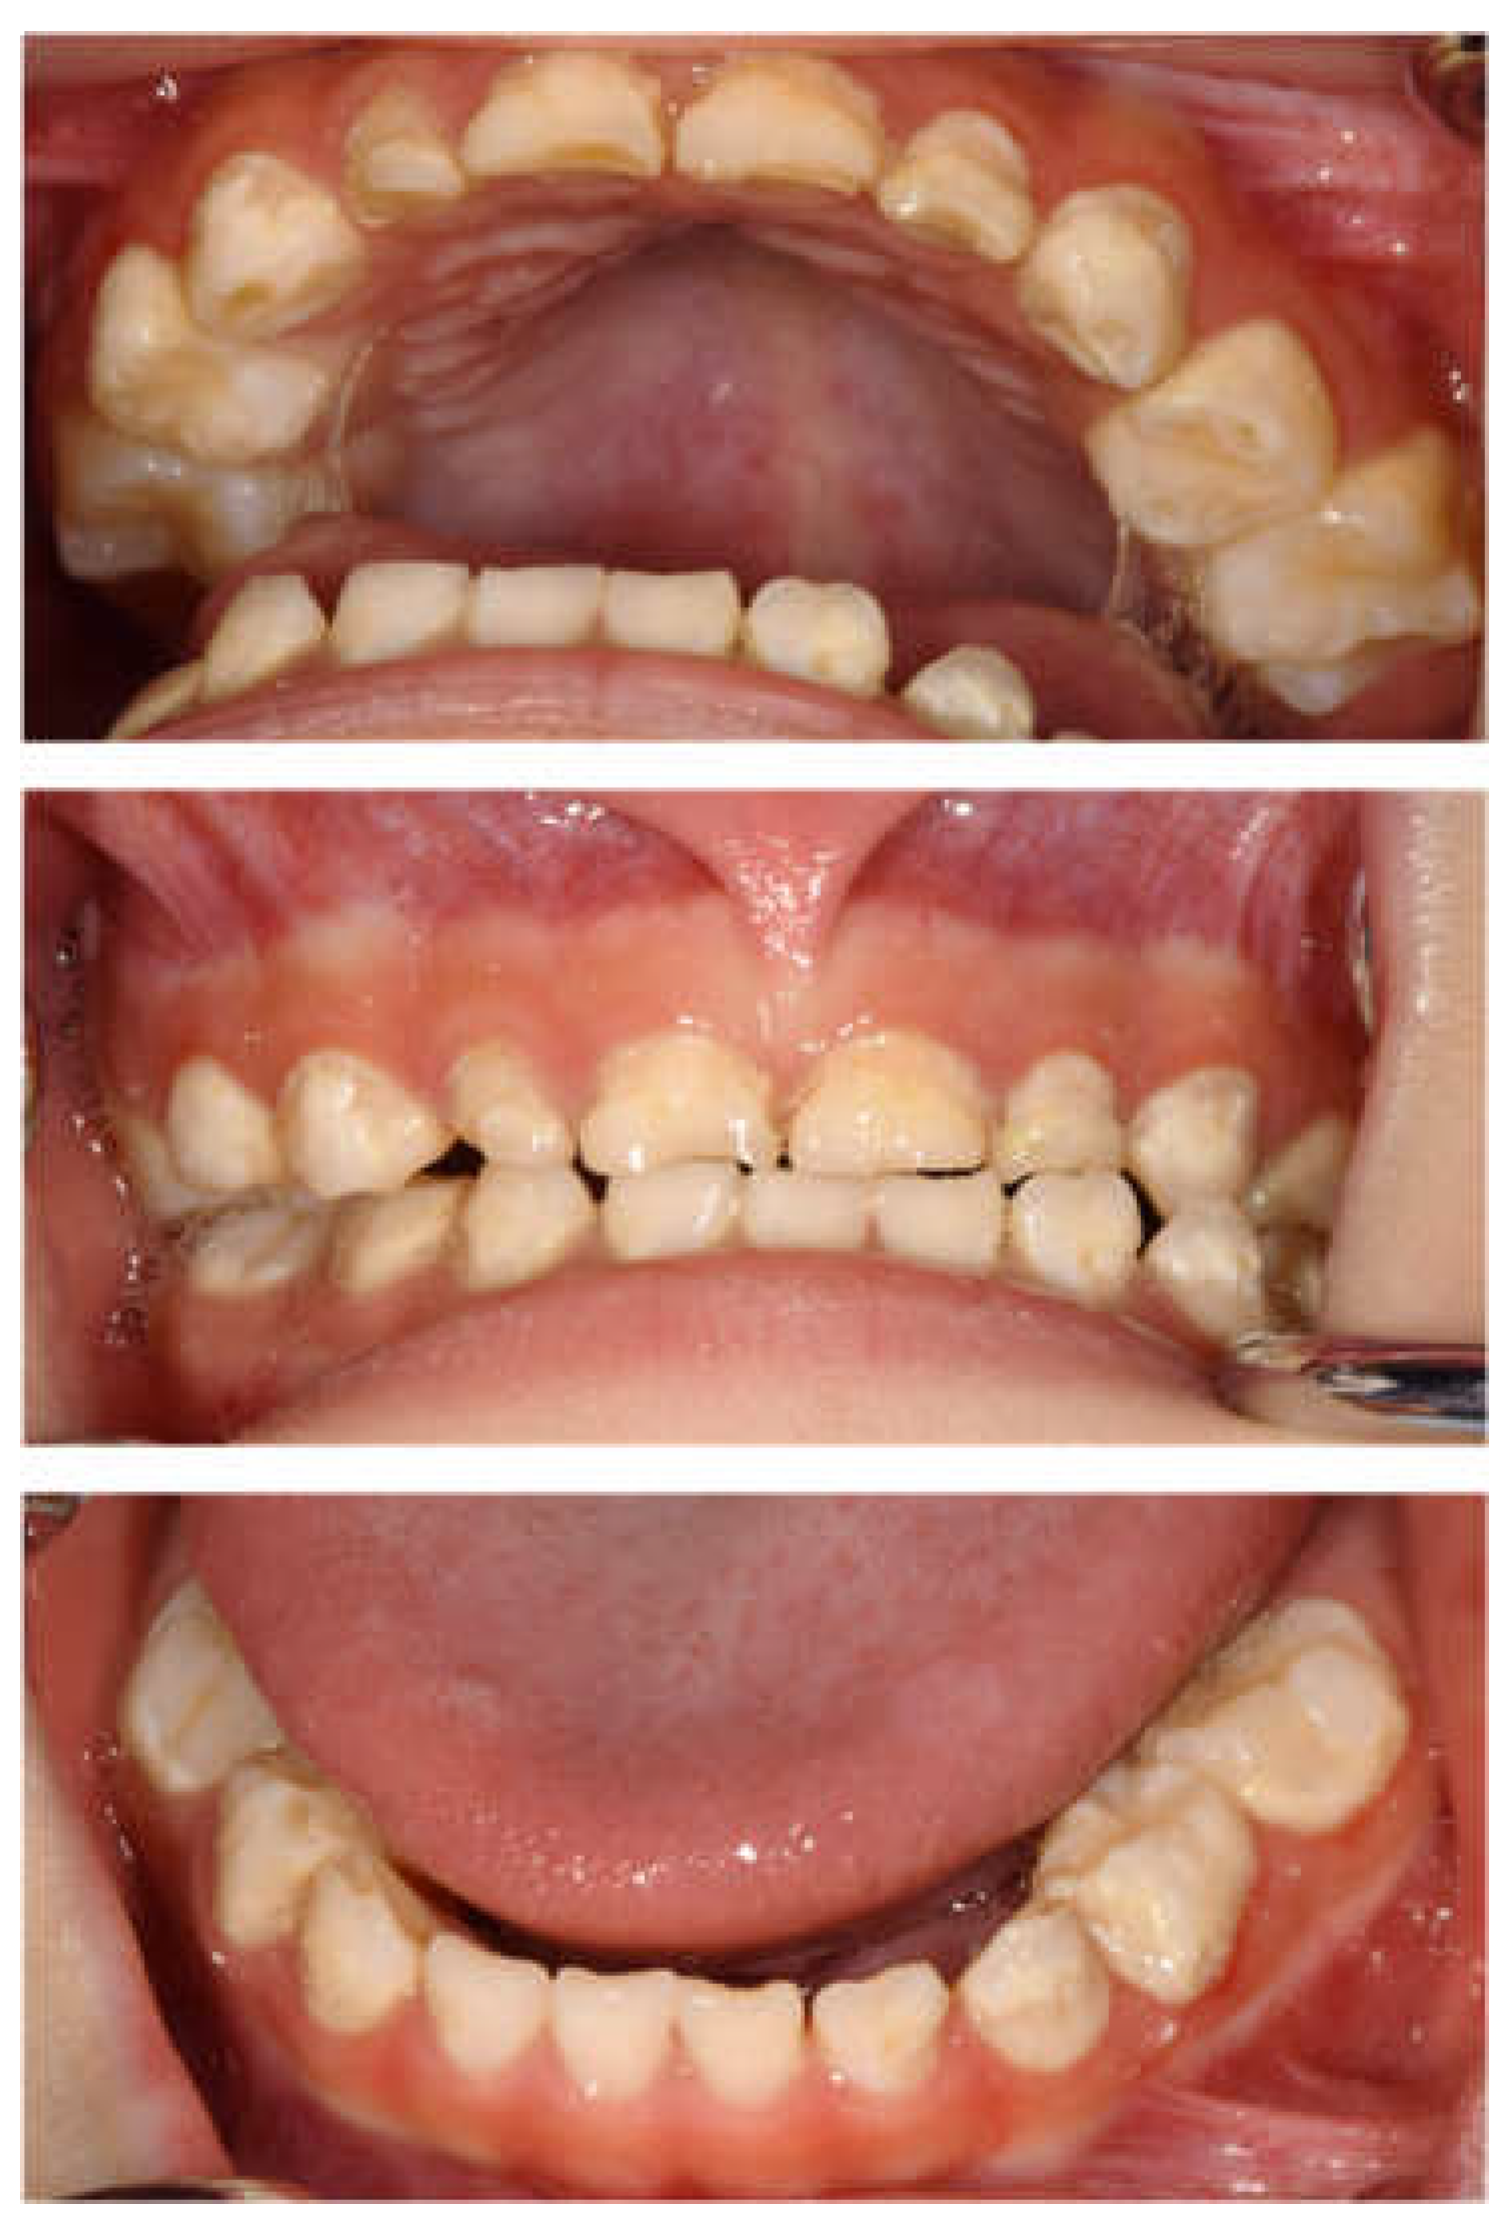

| Tooth | Diagnosis | Final Restoration |

|---|---|---|

| Maxilla | ||

| 51 | C2 | Resin-based composite crown |

| 52 | C2 | Resin-based composite crown |

| 53 | C2 | Resin filling |

| 54 | C2 | Preformed stainless-steel crown |

| 55 | C2 | Preformed stainless-steel crown |

| 61 | C2 | Resin-based composite crown |

| 62 | C2 | Resin-based composite crown |

| 63 | C2 | Resin filling |

| 64 | C2 | Preformed stainless-steel crown |

| 65 | C2 | Preformed stainless-steel crown |

| Mandible | ||

| 71 | C2 | No treatment |

| 72 | C2 | Resin filling |

| 73 | C2 | Resin filling |

| 74 | C2 | Preformed stainless-steel crown |

| 75 | C2 | Preformed stainless-steel crown |

| 81 | C2 | No treatment |

| 82 | C2 | Resin filling |

| 83 | C2 | Resin filling |

| 84 | C2 | Preformed stainless-steel crown |

| 85 | C2 | Preformed stainless-steel crown |